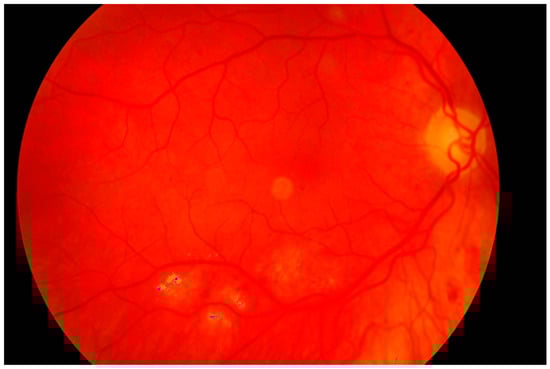

The second experiment was connected to checking whether our algorithm could be used for different images—ones with high resolution and high quality, and ones obtained by devices with worse parameters. Our database, obtained by the lower quality devices, contained 60 samples (50 healthy retinas and 10 with pathological changes). Thirty healthy samples were obtained with Digital Eye Center Microclear Handheld Ophthalmic Camera HNF whilst the rest of the low quality images were acquired with the d-Eye sensor. All of samples were acquired during medical examinations at Białystok University Clinical Hospital. Comparison was done to check if it was possible to observe pathological changes in retina images from worse devices. The sample image is presented in Figure 19.

The results showed that in the case of retina images from devices with lower precision, none of the healthy pictures was classified as a sample with pathological changes. Moreover, all retinas with diabetic retinopathy were classified as having pathological changes. This experiment confirmed that our solution can also be easily used with lower quality images. Moreover, it was pointed out that no additional adjustment of the proposed approach was needed.

Figure 19. Retina color image obtained by the device with worse parameters. No pathological changes exist.

Sensors 19 00695 g019